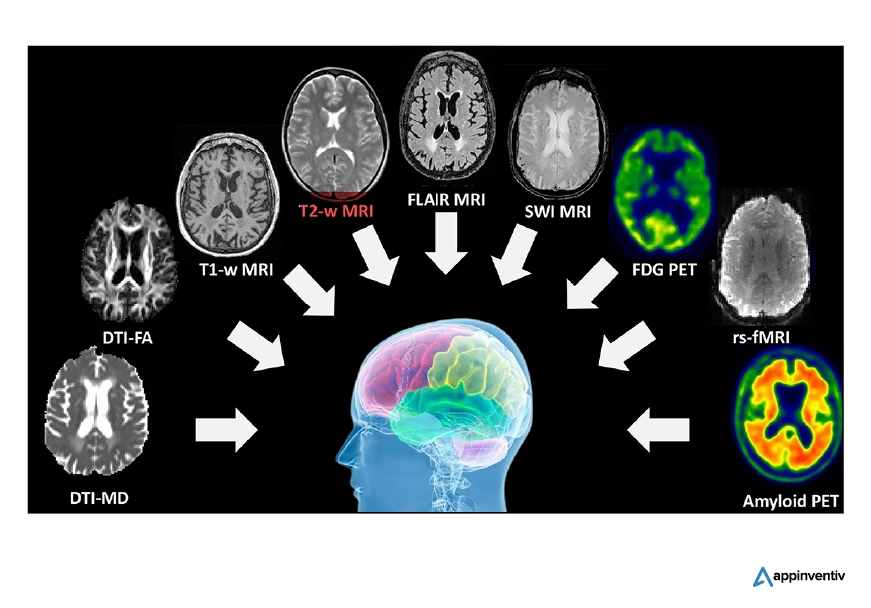

Imagistica Neurologică

Imagistica neurologică este un domeniu în care AI a avut un impact transformator. Prin algoritmi de învățare profundă, sistemele AI analizează eficient scanările creierului, accelerând detectarea anomaliilor precum tumorile sau accidentele vasculare cerebrale. Această tehnologie nu numai că îmbunătățește acuratețea diagnosticului, ci și îmbunătățește semnificativ viteza de interpretare, permițând o gestionare mai rapidă a pacientului. Aceste capabilități subliniază rolul utilizării AI pentru radiologie în domenii medicale complexe.

În special, aplicațiile inteligenței artificiale în radiologie sunt esențiale în identificarea modificărilor subtile în structura creierului care ar putea indica stadiile incipiente ale bolilor precum Alzheimer sau Parkinson. Prin automatizarea analizei imaginilor neurologice, AI permite diagnostice mai precise, susținând rezultate mai bune pentru pacienți și avansând în domeniul neurologiei.